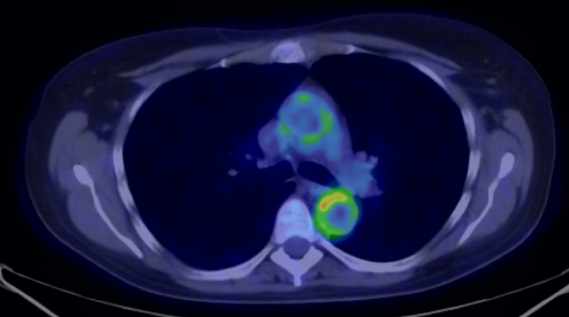

Test iframe

2. FDG PET Maximum Intensity Projection (MIP) image. There is a large biological contrast between the normal and the pathologic tissues. Right sided breast cancer, ipsilateral metastatic lymph nodes and multiplex metastases in the lung. Physiologically elevated FDG uptake is seen in the brain, salivary glands, tonsils, liver and the spleen as well as in the bone marrow and at certain segments of the intestines. Also, there is increased FDG activity in the kidneys and the urinary bladder due to excretion.